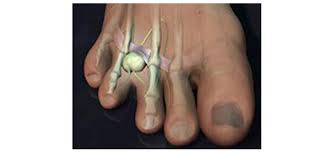

발목터널증후군

발목터널증후군은 발목을 지나는 신경이 손상을 입어 발 전체에 찌릿찌릿한 통증을 유발하는 질환입니다. 특히 40세 이상의 여성에서 발병률이 높습니다.